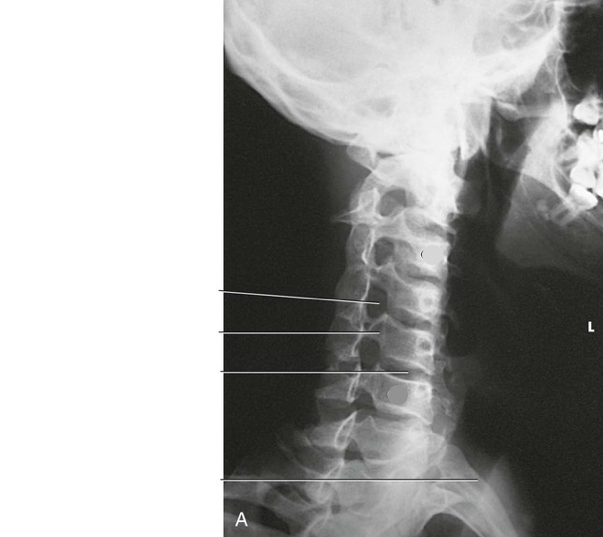

Question 3

Question

Label the image

Image:

Answer

C5

mandibular rami

body

inferior articular process

superior articular process

intervertebral disk space

zygapophyseal joint

vertebra prominens